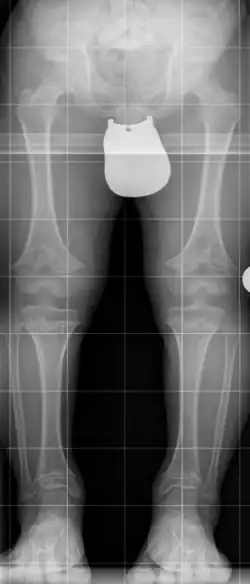

Radiologische Kriterien sind:

- Verbreiterte Metaphysen bei normalen Epiphysen

- Überproportional verkürzter Humerus und Femur

- Schmales Kreuzbein, breite Beckenschaufel mit horizontalem und breitem Pfannendach

- Verschmälerter Abstand der Bogenwurzeln nach kaudal zunehmend, verkürzte Pedikel mit eventueller Spinalstenose, keilförmige Deformierung der Wirbelkörper

- Brachydaktylie mit Dreizackhand[5]

Die Achondroplasie führt zu einem disproportionierten Kleinwuchs. Da die unübliche Knorpelbildung insbesondere in den Röhrenknochen eine regelgerechte Entwicklung nicht möglich werden lässt, sind stark verkürzte Extremitäten bei normaler Rumpfgröße charakteristisch. Das Längenwachstum ist bei dagegen nahezu normalem Dickenwachstum gestört.

- häufig O-Beine oder X-Beine